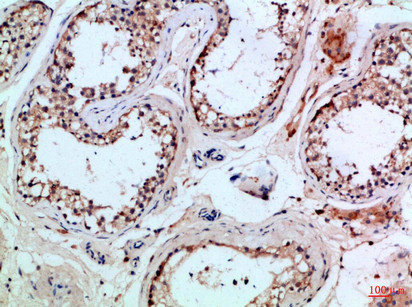

Immunohistochemical analysis of paraffin-embedded Human-testis, antibody was diluted at 1:100